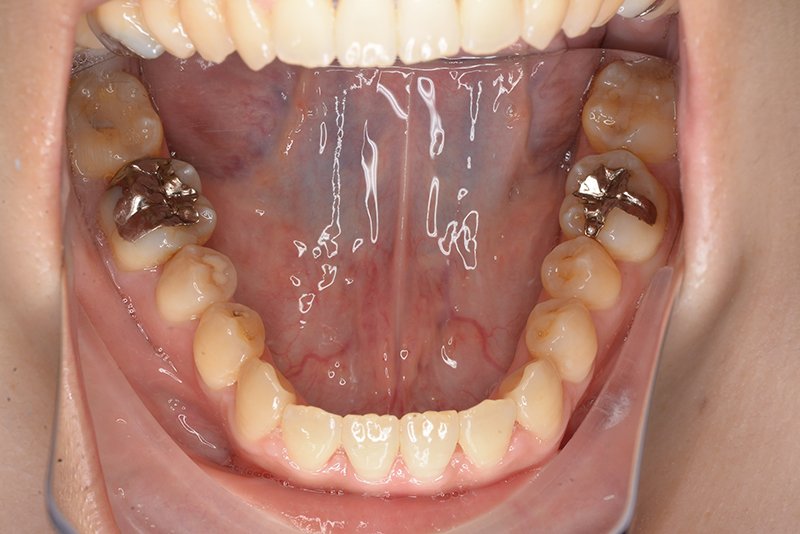

初診時

FP・IOP

口腔内所見 臼歯関係はⅢ級、下顎歯列はスピーカーブによって前歯は舌側へ倒れこみつつ挺出しておりover jet-2.5mm、over bite3.0mmと反対咬合を呈していた。

パノラマ所見 上顎両側8が存在していた。下顎臼歯は近心傾斜が認められた。